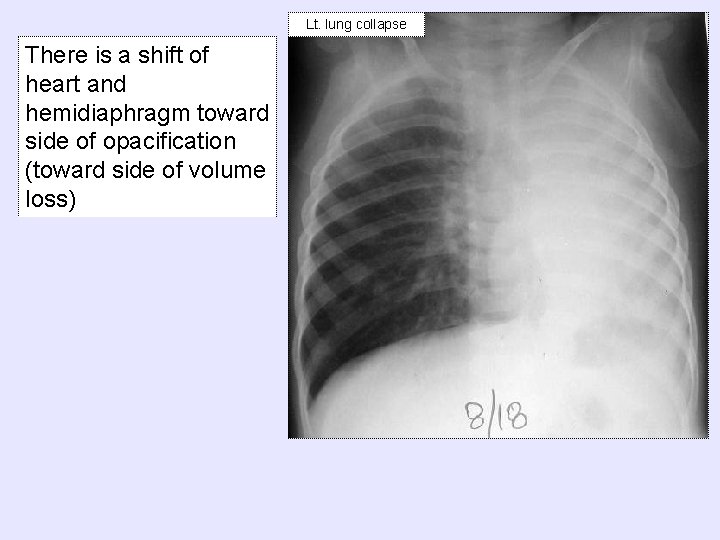

Lt. lung collapse There is a shift of heart and hemidiaphragm toward side of

Lt. lung collapse There is a shift of heart and hemidiaphragm toward side of opacification (toward side of volume loss)